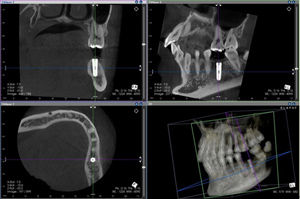

下顎の親知らずの歯は横に生えたり、顎の骨の中に埋まっている場合が多いです。抜歯するときは歯根の位置や方向、下顎骨内にある神経の位置、歯根との距離を正確に確認することが非常に重要です。

上顎の親知らずは、上顎洞という組織に近接しています。これは副鼻腔と言われ鼻腔に交通している空洞です。上顎洞は親知らずの直上に位置しているため、抜歯後の上顎洞への穿孔、抜歯した歯が上顎洞へ迷入しないよう等の細心の注意を払う必要があります。下顎の親知らずとは違った注意を要しますので、上顎洞との三次元的位置関係、距離を考慮して抜歯を行う必要があります。

CT撮影することによって周囲の組織との関係を立体的に精密かつ正確に診断できますので、親知らずの抜歯がより安全に行うことができます。